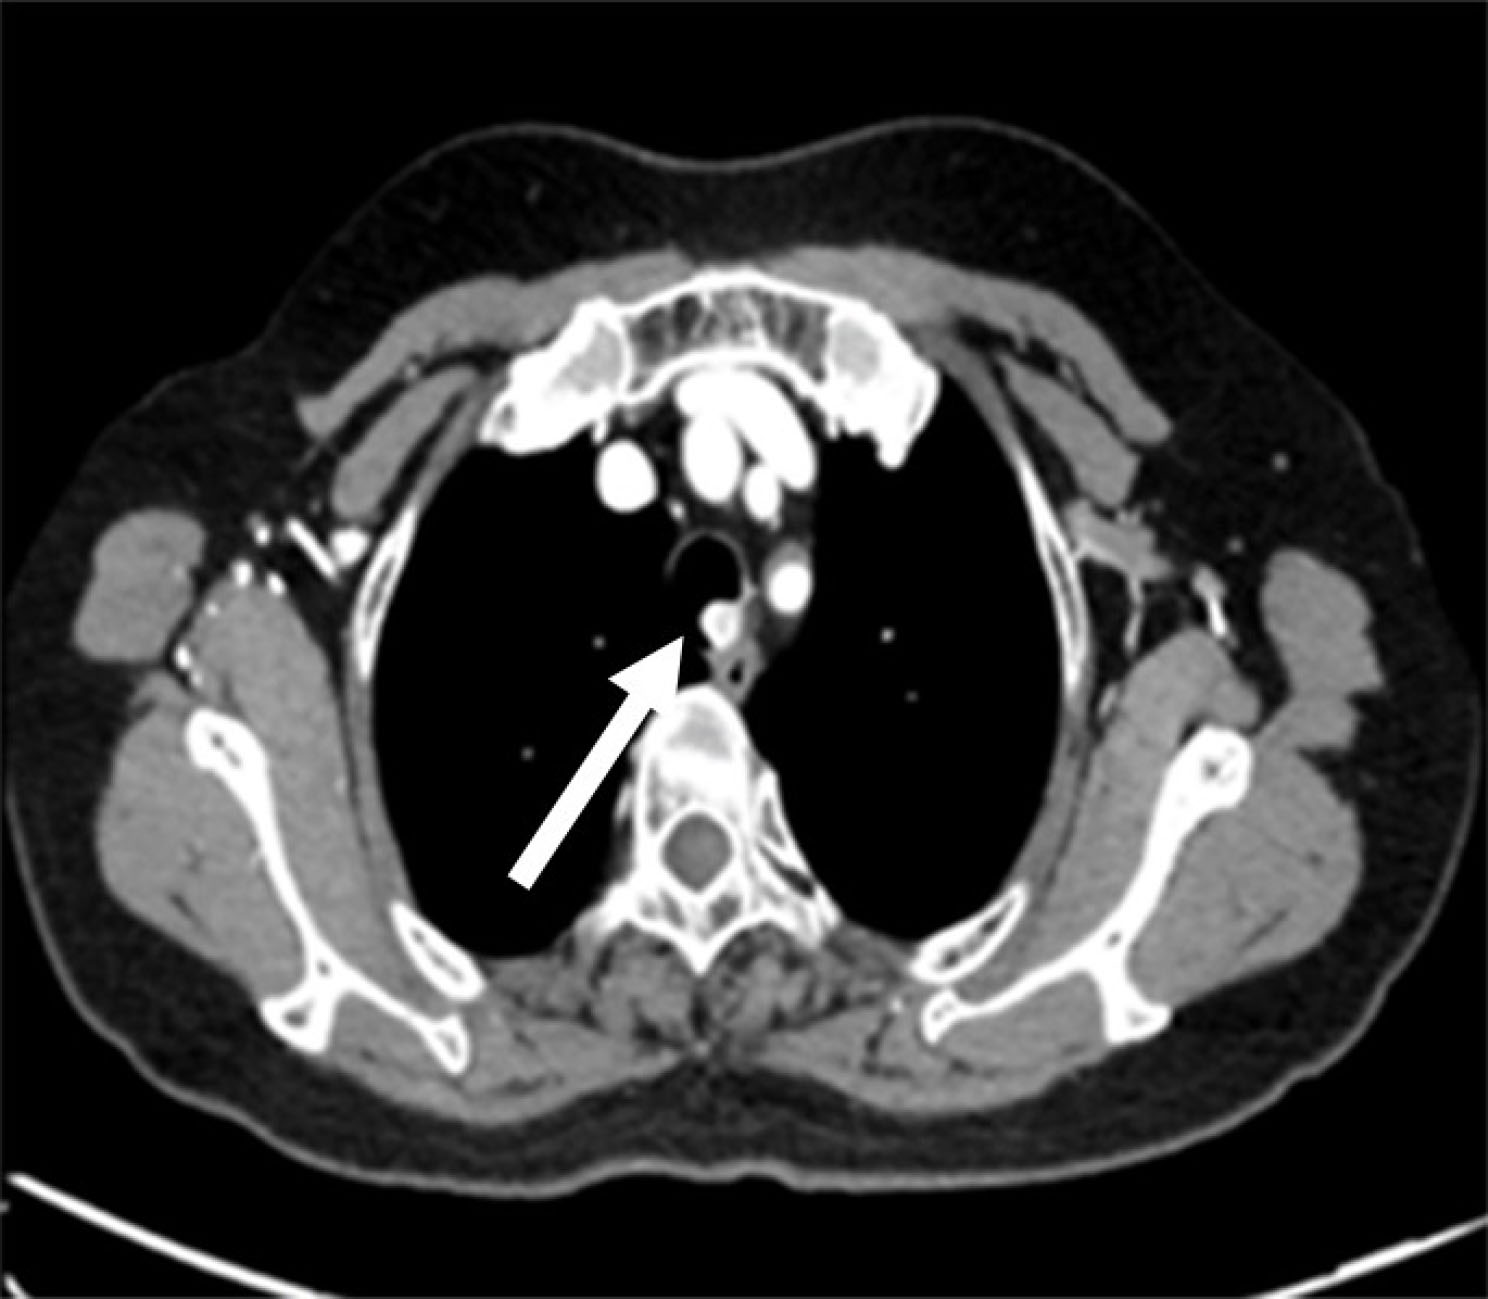

Figure 2.

Chest computed tomography showing low-density mass protruding into the airway lumen (white arrow).

A 52-year-old patient was admitted to our hospital with a seven-day history of recurrent hemoptysis. The clinical symptoms occurred occasionally, producing up to 15 mL of sputum stained with fresh blood after coughing. She had no history of an underlying disease. A physical examination of the lung revealed rough breathing sounds in the lungs. The laboratory findings revealed no obvious abnormal values, including for liver and renal function, C-reactive protein and complete blood count. Bronchoscopy confirmed the presence of an ileal mass with rich vascularity (Figure 1). Chest computed tomography (CT) showed a mass protruding into the airway lumen (Figure 2). After enhancement, homogeneous enhancement was observed in the areas (Figure 3).